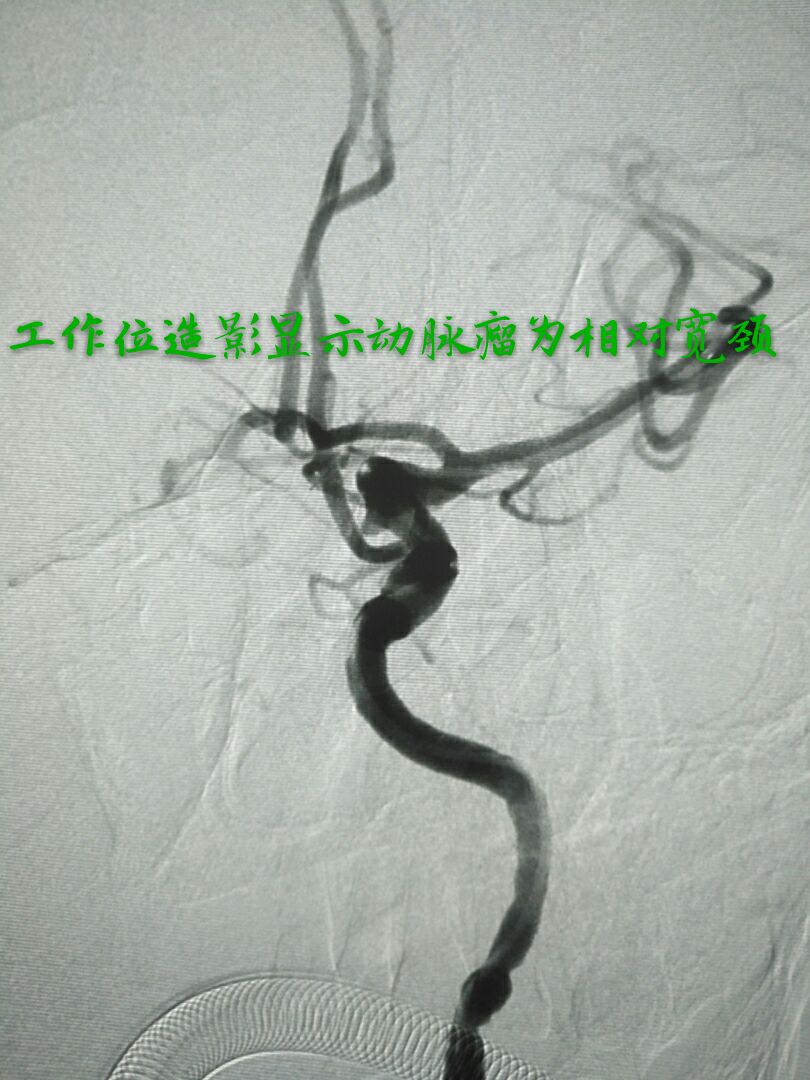

病例八:老年女性,间断性头痛、头晕1年,DSA发现右侧大脑前动脉A3段动脉瘤,形态不规则,宽颈

支架辅助下动脉瘤致密栓塞,难点:动脉瘤位置较远,通路迂曲,支撑导管不稳定